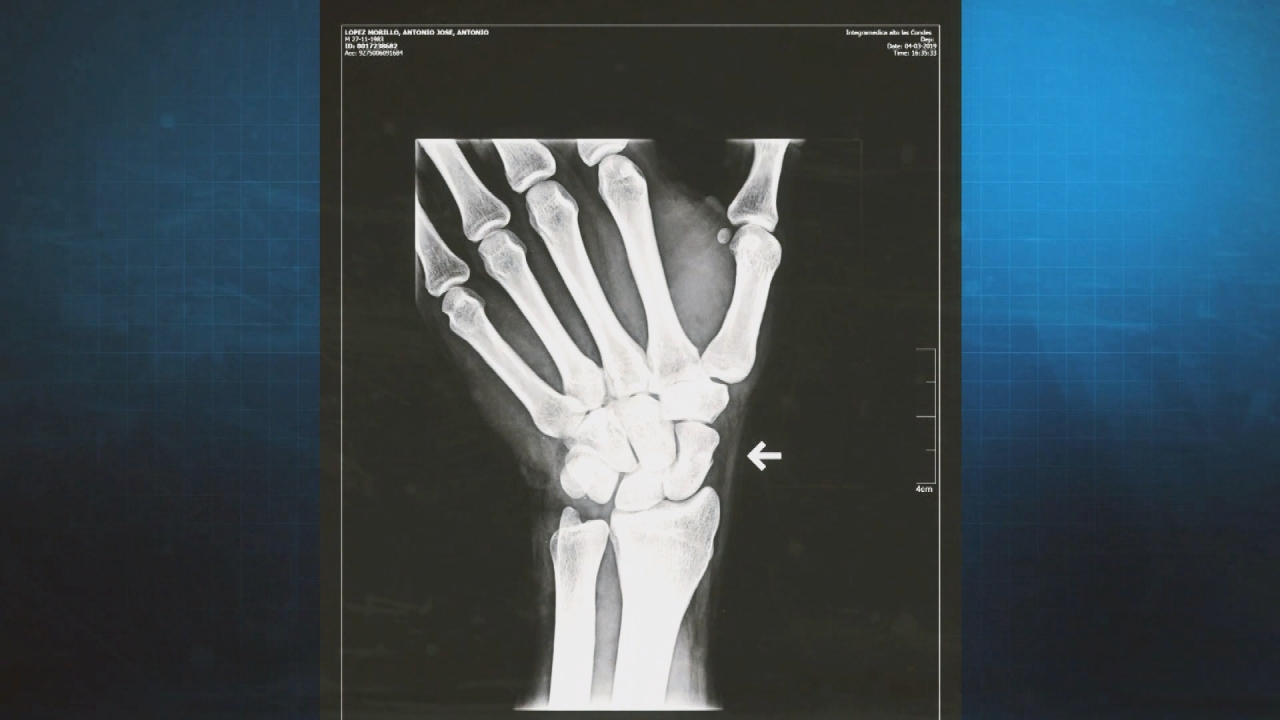

Las fracturas de muñecas son las lesiones que más se repiten en un rango de edad entre los 15 y 30 años, recalcan los especialistas.

El doctor Francisco Andrade, traumatólogo de la Clínica Las Condes, asegura que se ha visto “un aumento en la consulta y sobretodo de lesiones más graves en las extremidades superiores. Incluso hemos tenido que intervenir algunos pacientes producto de fracturas”.